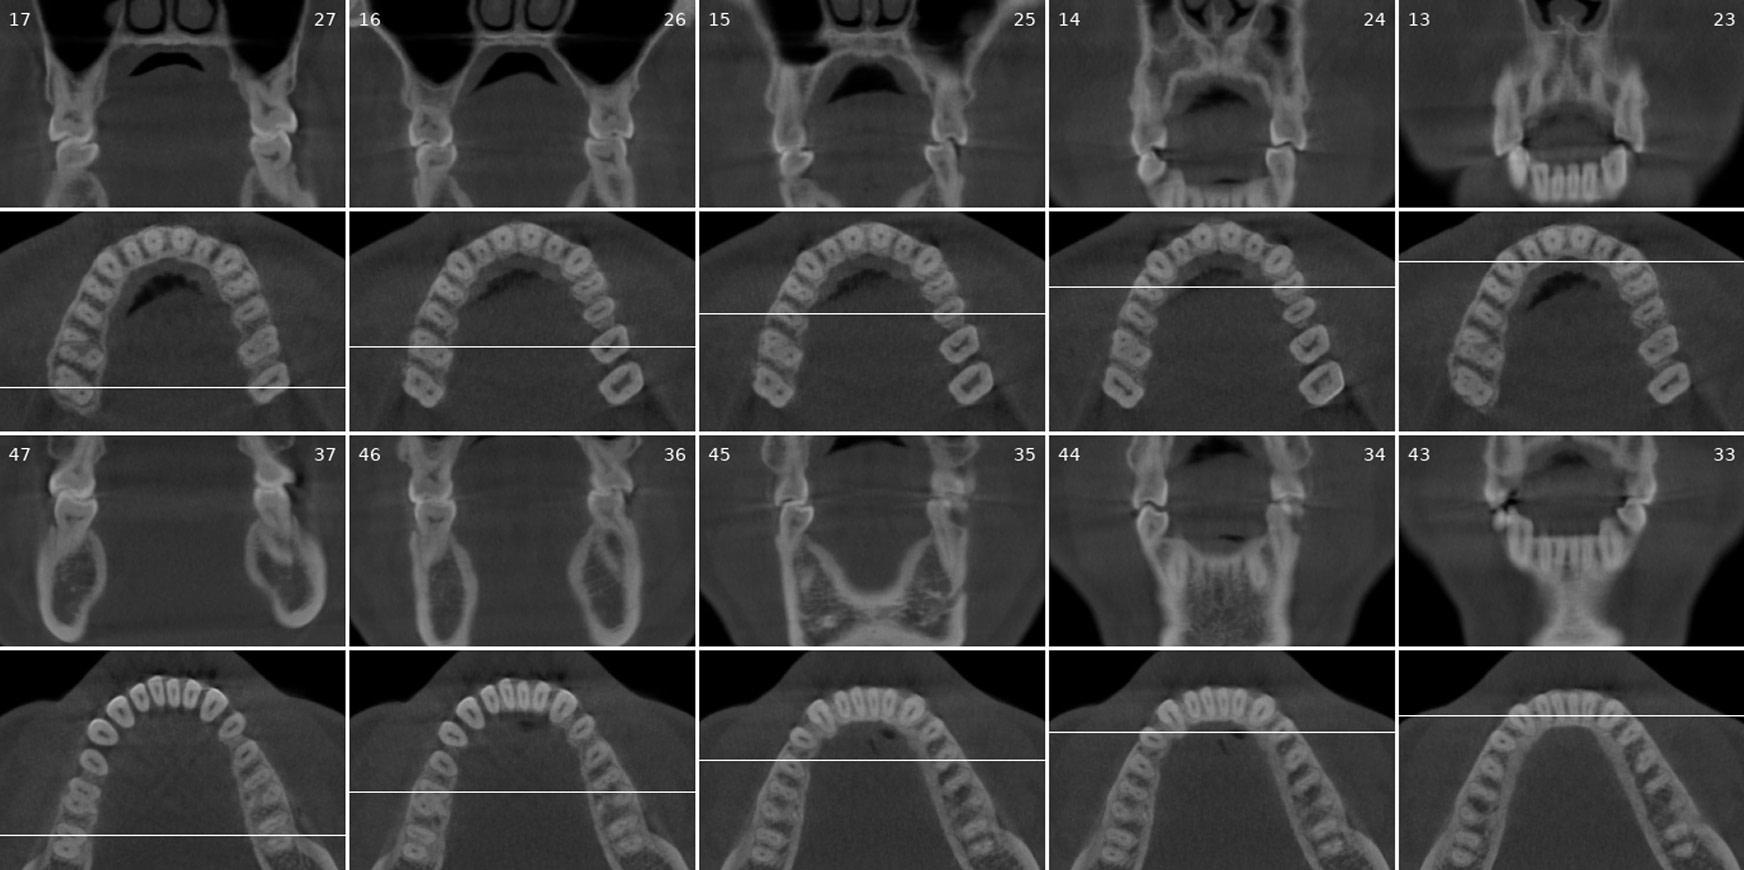

Diagnocat generates OPG and frontal and lateral cephalometric reconstructions from the CBCT data.

Tracings of the maxilla, mandible, central incisors, canines and molars. All automatically.

Cross-sectional and coronal views of teeth show torque and buccolingual relationships such as crossbite.

The orthodontic report generates OPG and front/lateral cephalograms. These are not as sharp as true OPG and cephalograms. Tracings of the maxilla, mandible, central incisors, canines, and molars are automatically produced on the generated frontal/lateral cephalogram.

I showed the orthodontic report to an orthodontist colleague. She found the tracings to be fairly accurate compared to a real lateral cephalogram of the same patient. She did further tracings on the generated lateral ceph and advised it was difficult to visualize points such as Nasion, ANS, A Point, Condylion, and Orbitae and visualize the fourth vertebrae to determine peak growth phase. Furthermore, other orthodontic software can automatically calculate skeletal/dental relationships, planes, and angles.